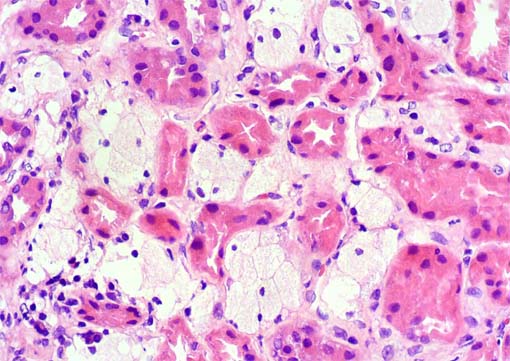

Figura 3.

H&E, X400.